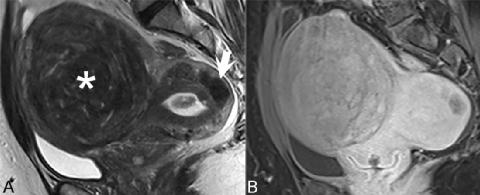

▲ 图74.4

在T2WI上对平滑肌瘤进行最佳评估,如图74.4A所示,其中存在多个不均匀病变。基底部病变(白色箭头)具有特征性外观T2WI上可见界限清楚的肿块,相对子宫肌层呈低信号。低信号与平滑肌和纤维含量相关,而病变因其周围压迫子宫肌层的假包膜而明显。在(B) CE T1WI上,与正常子宫相比,平滑肌瘤均表现出边界清楚但增强减弱。平滑肌瘤增强情况确实各不相同,高强化意味着子宫动脉栓塞结果良好。T2WI上的高信号病灶在图74.4中最大的平滑肌瘤中明显可见(星号),与透明样变性、脂肪变、囊变、出血、粘液和粘液性变性相关,无特异性。然而,出血性变性可通过T1WI上的高信号和缺乏对比增强得到可靠识别——这些特征预示着子宫动脉栓塞的预后不良。细胞平滑肌瘤在T2WI上也可能表现为高信号,并表现出强烈的对比增强。平滑肌瘤的鉴别诊断因病变部位而异:浆膜下病变可能与卵巢纤维瘤混淆,两种病变均为良性,而子宫肌层收缩也可能表现为子宫肌层低信号,推测是由于收缩组织内灌注减少所致。这种收缩使子宫内膜变形,保留了子宫轮廓。罕见的平滑肌肉瘤不能可靠地与良性平滑肌瘤区分开来,其显著特征是体积突然增大。然而,它们的边界可能不太明显,并可能表现出扩散受限、对比增强、坏死或出血。局灶性子宫腺肌病是肌壁间平滑肌瘤的主要鉴别诊断因素。图74.5显示了(A)矢状位和(B)轴位FS T2WI上腺肌瘤的典型表现。在两幅图像中,病变(白色箭头)表现为结合带边界不清的增厚(> 8 mm),信号强度降低与平滑肌增生相关。子宫内膜缺乏占位效应以及

从内膜到子宫肌层的高信号病灶和条纹(可能代表出血或异位子宫内膜)也是特征性的。子宫腺肌病也可表现为与异位子宫内膜相对应的高信号散在病灶。出血灶在T1WI上可能呈高信号。在CE T1WI上,腺肌瘤的增强可能不如正常子宫肌层迅速,并且由于异位子宫内膜腺缺乏增强,呈现所谓的瑞士奶酪外观。

▲ 图74.5